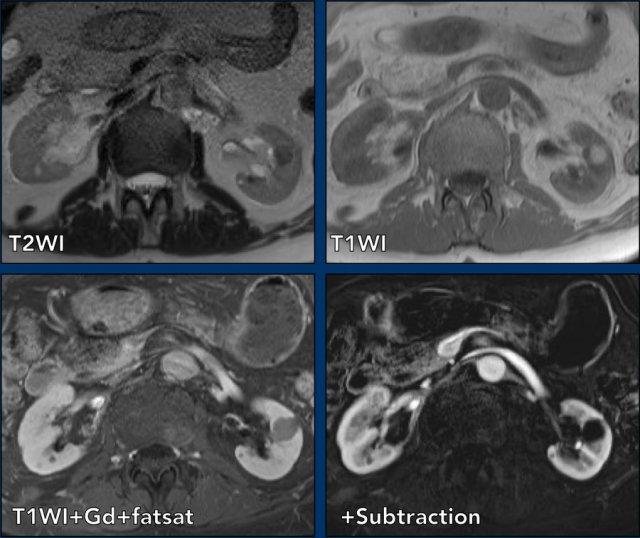

MRI của cùng bệnh nhân.

Tổn thương giảm tín hiệu trên chuỗi xung T2W và tăng tín hiệu trên chuỗi xung T1W.

Không có ngấm thuốc tương phản từ trên chuỗi xung trừ (subtraction).

Trên MRI, tổn thương được xác nhận là Bosniak II.